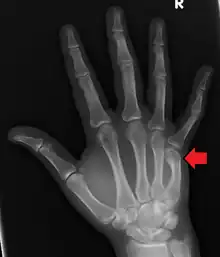

| Other names: Metacarpal neck fracture of the little finger, scrapper's fracture,[1] bar room fracture, street fighter's fracture[1] | |

| Boxer's fracture of the 5th metacarpal head from punching a wall | |